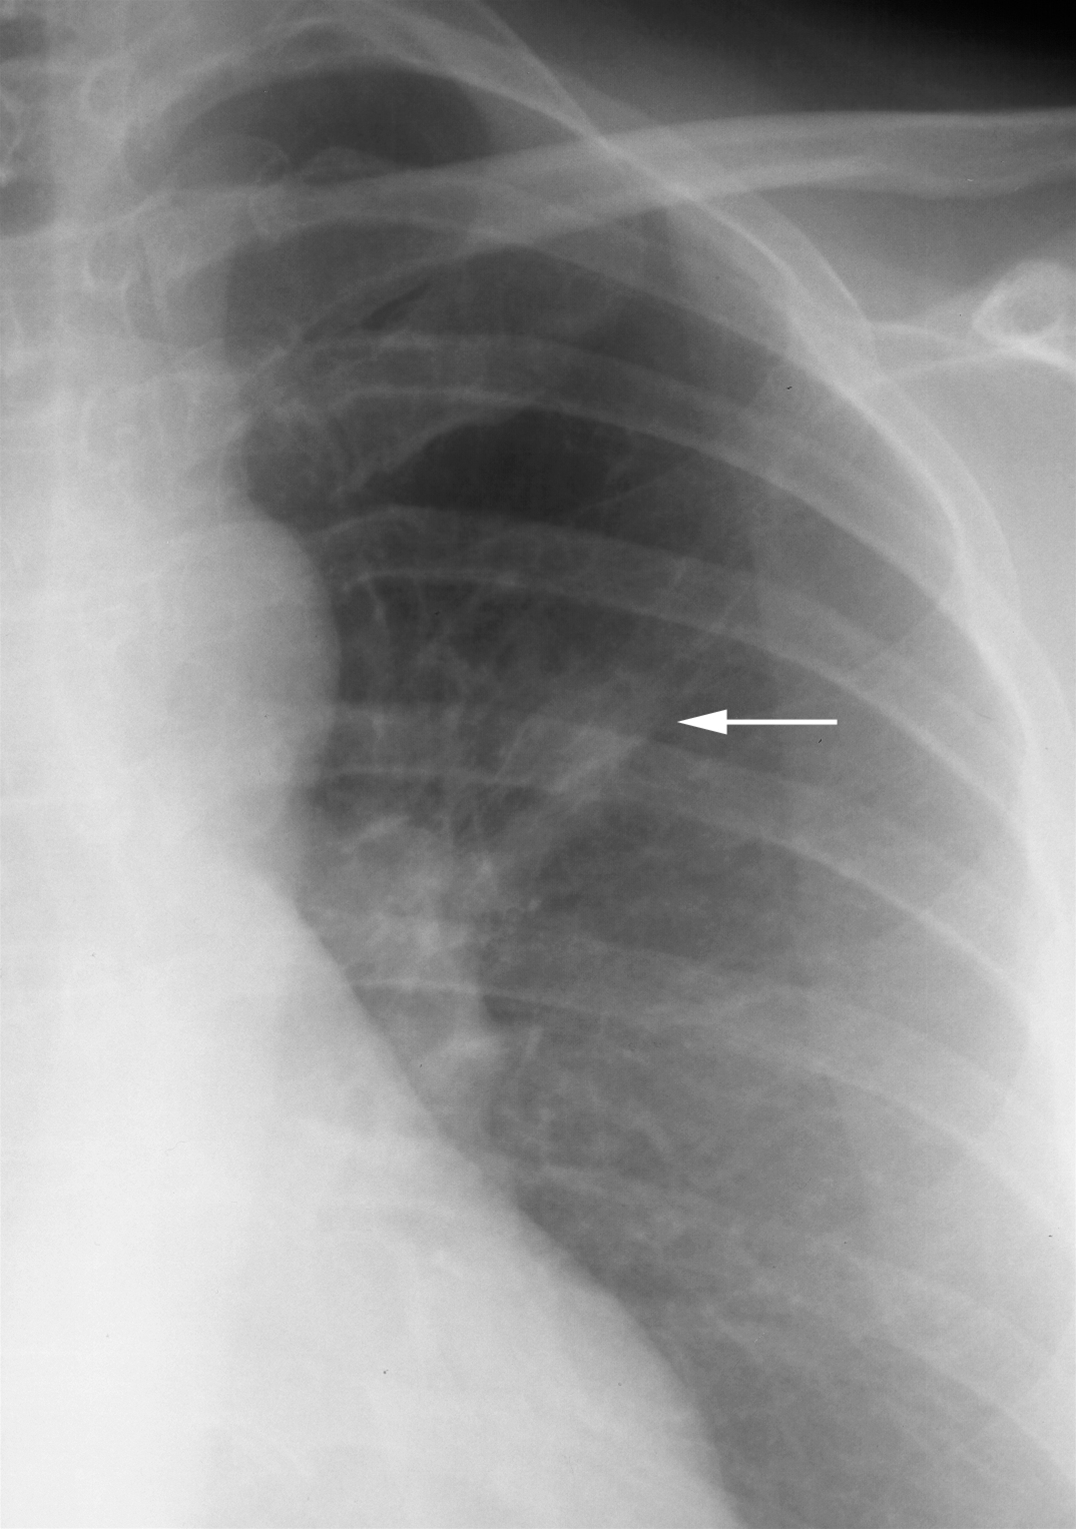

Røntgenbilledet viser en lille og lidt uskarp, afgrænset tumor i venstre lunges overlap (pil). Samme tumor som på billedet "Lungekræft CT".